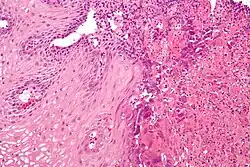

Microscopic Slide of Infectious Esophagitis

Infectious esophagitis

Esophagitis happens due to a viral, fungal, parasitic or bacterial infection. More likely to happen to people who have an immunodeficiency. Types include:

Microscopic Slide of Eosinophilic Esophagitis

Eosinophilic esophagitis

Eosinophilic esophagitis is caused by a high concentration of eosinophils in the esophagus. The presence of eosinophils in the esophagus may be due to an allergen and is often correlated with GERD. The direction of cause and effect between inflammation and acid reflux is poorly established, with recent studies (in 2016) hinting that reflux does not cause inflammation.[6] This esophagitis can be triggered by allergies to food or to inhaled allergens. This type is still poorly understood.